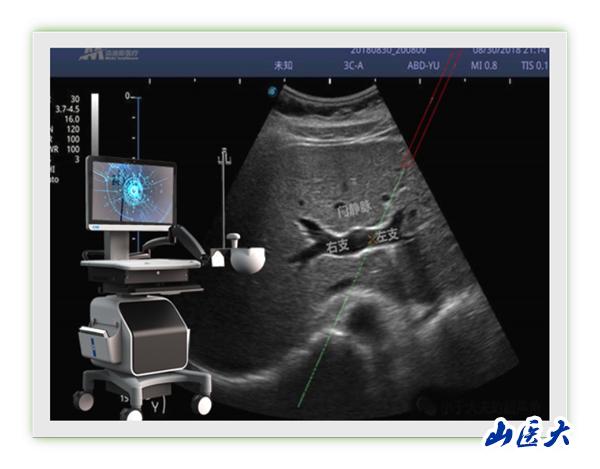

近日,第一醫院腫瘤與血管介入科馮對平主任團隊成功完成山西省首例超聲用電磁定位穿刺引導TIPS術。該技術將超聲圖像與電磁信號相融合,突破傳統超聲引導必須在平面內或平面外穿刺制約,能夠在任意位置、任意角度、任意平面穿刺靶點,真正實現實時三維穿刺導航。更為重要的是,該技術具有我國自主知識產權。馮對平說:“該新型穿刺引導技術能夠大大降低TIPS術中門靜脈穿刺難度,提高TIPS手術成功率,同時術者及患者受X線輻射時間也明顯縮短,值得進一步推廣應用?!?/p>